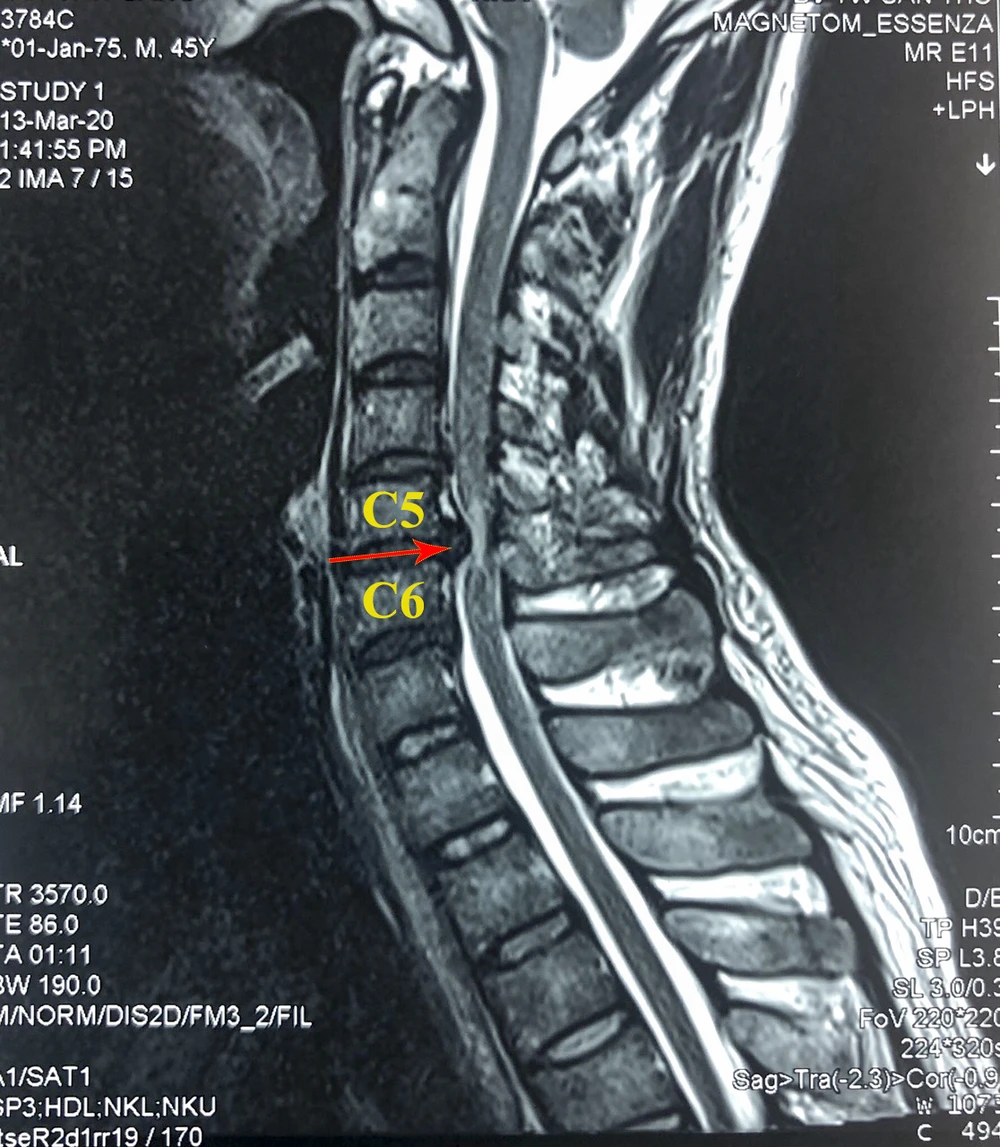

Qua kiểm tra và hội chẩn, các bác sĩ nhận định bệnh nhân mắc bệnh lý tủy cổ do thoát vị đĩa đệm tầng C5-6 chèn ép vào tủy sống cạnh trung tâm lệch phải. Bệnh nhân được chỉ định thay đĩa đệm nhân tạo đốt sống cổ ở tầng C5-6.

Hình ảnh trước và sau phẫu thuật thay đĩa đệm cột sống cổ 1 Hình ảnh trước và sau phẫu thuật thay đĩa đệm cột sống cổ 2

Hình ảnh trước và sau phẫu thuật thay đĩa đệm nhân tạo cột sống cổ.